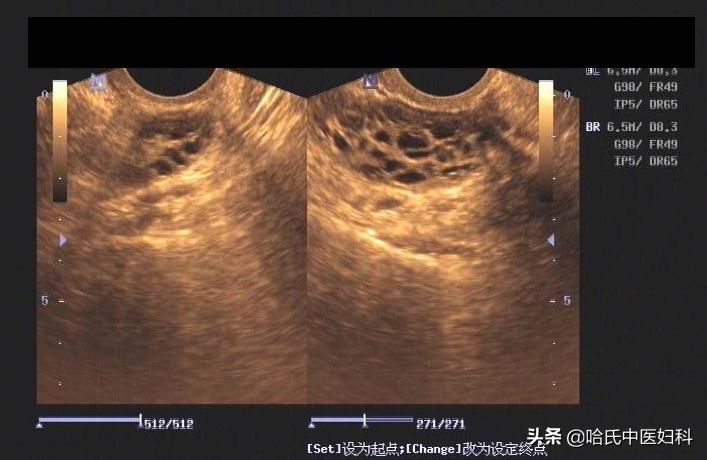

多囊卵巢综合征患者,多存在卵泡发育不良, 卵巢内可见多个发育不成熟的小卵泡,而且年龄较小的患者,通过B超检查多数可见子宫发育小。

辅助检查:B超示子宫稍小27 mm×23 mm×30 mm,双侧卵巢内可见直径<9 mm以下滤泡12个以上,呈项链状分布,提示多囊卵巢综合征;甲状腺功能未见异常;